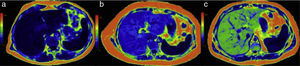

Steatosis quantification in color cartographyLiver fat quantification can also be carried out through cartography or a color map. It provides rapid visual appreciation of the existence of steatosis and the measurements are made directly on the image (Figure 7a, b, and c).

Color maps in 3 patients with different steatosis grades: a) patient with normal fat content: the dark blue of the liver corresponds to the lower part of the colorimetric scale and to a quantification below 6% (normal); b) in this patient the light blue is higher on the scale and the fat content is increased to an average 17%; c) the image in the third patient assigned green to the liver, which is indicative of a high fat content and was quantified at 33%.

The different colors of the map correspond to the distribution and intensity of the infiltrate that can be diffuse or regional (“geographic steatosis” or “in patches”), or even be present in a focal lesion, such as occurs in lipomas and some adenomas and hepatocellular carcinomas.

Cartography facilitates the analysis of fat content by comparing the colors of the colorimetric bar that is attached to the image. In our equipment, dark blue tones correspond to the lowest lipid concentration. Light blue and green tones indicate larger quantities of infiltrate, and yellow and red tones appear in the highest concentrations. The cartography image covers the entire circumference of the abdomen, and thus the subcutaneous fat and the peritoneal and perirenal spaces are also highlighted in red tones.

There are other techniques for evaluating parenchymal iron. Among them, the so-called MRI R2 and R2* technique can provide parametric images that reflect the iron content in the liver and spleen (Figure 9). The results of comparisons with liver biopsy have been dissimilar due to the heterogeneity of the iron deposits. They are generally similar, but MR has the obvious advantages in treatment follow-up and patient preference because of its noninvasiveness.42,43

Hemochromatosis. a) In the colorimetric map, the reds correspond to the higher part of the scale, indicating greater iron concentration in the liver parenchyma. b) Also note the red dot in the amplified image of the spleen produced by the Gamna-Gandy siderotic bodies. c) In addition, the anatomic image in T1 of this patient showed decay of the parenchymal signal of the pancreas (arrow) and the presence of enlarged peripancreatic lymph nodes (arrows) in relation to the hemochromatosis (d).